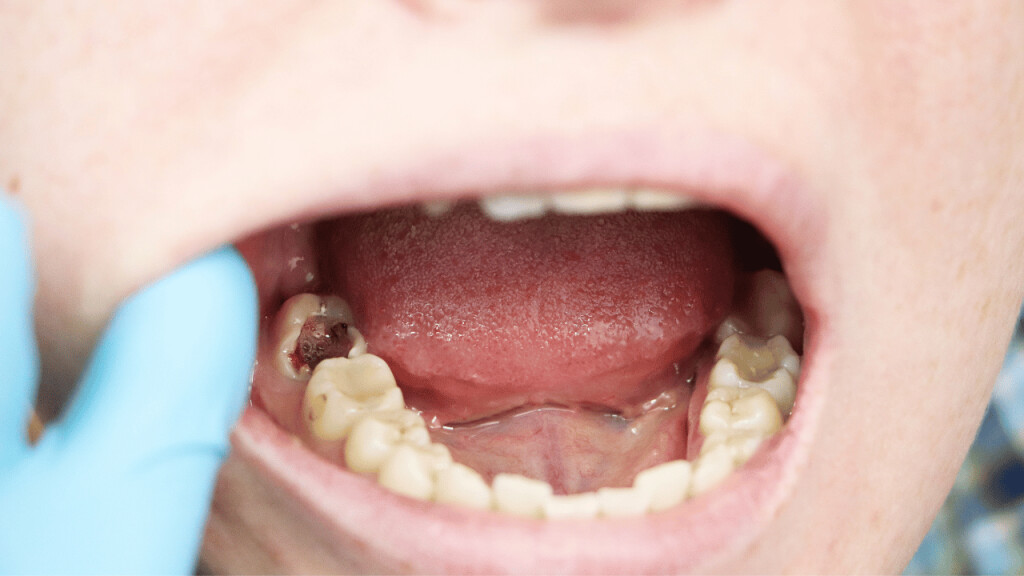

Wisdom teeth promotes Gum Disease

It is a challenging task to clean the area in which the third molars have erupted. Therefore they are at a greater risk of acquiring the periodontal problems. The gum diseases are usually caused by bacteria, and when a tooth can’t be precisely cleaned on a regular basis, the dental plaque gets accumulated around the tooth, which may lead to further complications.

Tooth Decay

The fully impacted or the partially impacted wisdom teeth are at greater risk of tooth decay, than other teeth. This usually happens, because of the location of the wisdom tooth, especially towards the back of the mouth, which is hard to clean. Moreover, since it lies at the back of the mouth, there are chances of food getting easily trapped between the gums and the tooth, promoting the growth of bacteria.